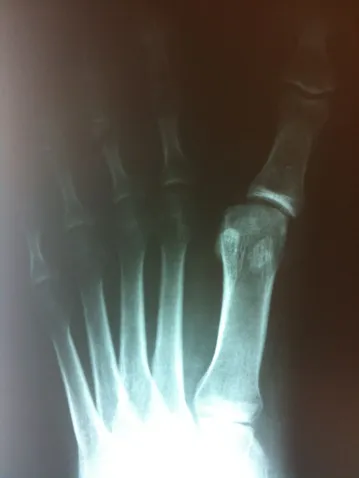

Varus position great toe after bunion surgery, the great toe is deviated laterally away from the lesser toes (left). Surgical procedure performed involved soft tissue correction and temporary fixation with a Kirschner wire (center). Several weeks after surgery the wire is removed and the great toe is now in rectus (straight) position.